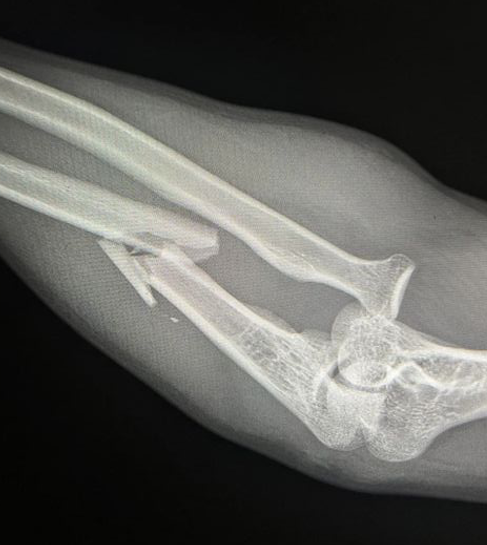

Ongoing anterior radial head dislocation after olecranon plating, treated with lateral approach and open reduction